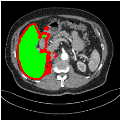

Our primary findings comparing the proposed model to baseline fully-supervised models when segmenting the liver from the LiTS dataset are reported in Table 1. The reported results demonstrate that our SAM-Mix model consistently achieves higher Dice scores compared to the fully supervised baselines as well as the two-stage SAM-PP method. Against U-Net, the best-performing fully supervised method, the SAM-Mix variant trained on 50 segmentation labeled slices (SAM-Mix-50), achieves a Dice score improvement of 5.9%. In terms of Hausdorff distance, while the fully-supervised baselines do slightly outperform SAM-Mix-5 and SAM-Mix-100, SAM-Mix-50 does achieve a lower Hausdorff distance by 22.38%. Qualitative evaluation as shown in Figs. 3 further affirms the superiority of SAM-Mix over baseline and existing fully-supervised methods as well as the two-stage SAM-PP variants. Furthermore, the boxplot visualization in Fig. 2 showcases consistently improved performance by SAM-Mix outperforming all the fully supervised and semi-supervised methods.

![]() |

| U-Net | nnU-Net | TransU-Net | SAM-PP-0 | SAM-PP-5 |

| SAM-PP-50 | SAM-PP-100 | SAM-Mix-5 | SAM-Mix-50 | SAM-Mix-100 |